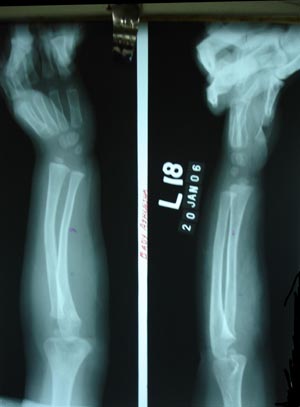

Colles’ fracture 1

Here it reveals enhancement of curvature (Bending) It shows the bony trabeculae are interrupted across the fracture site. It may show step in the cortex.